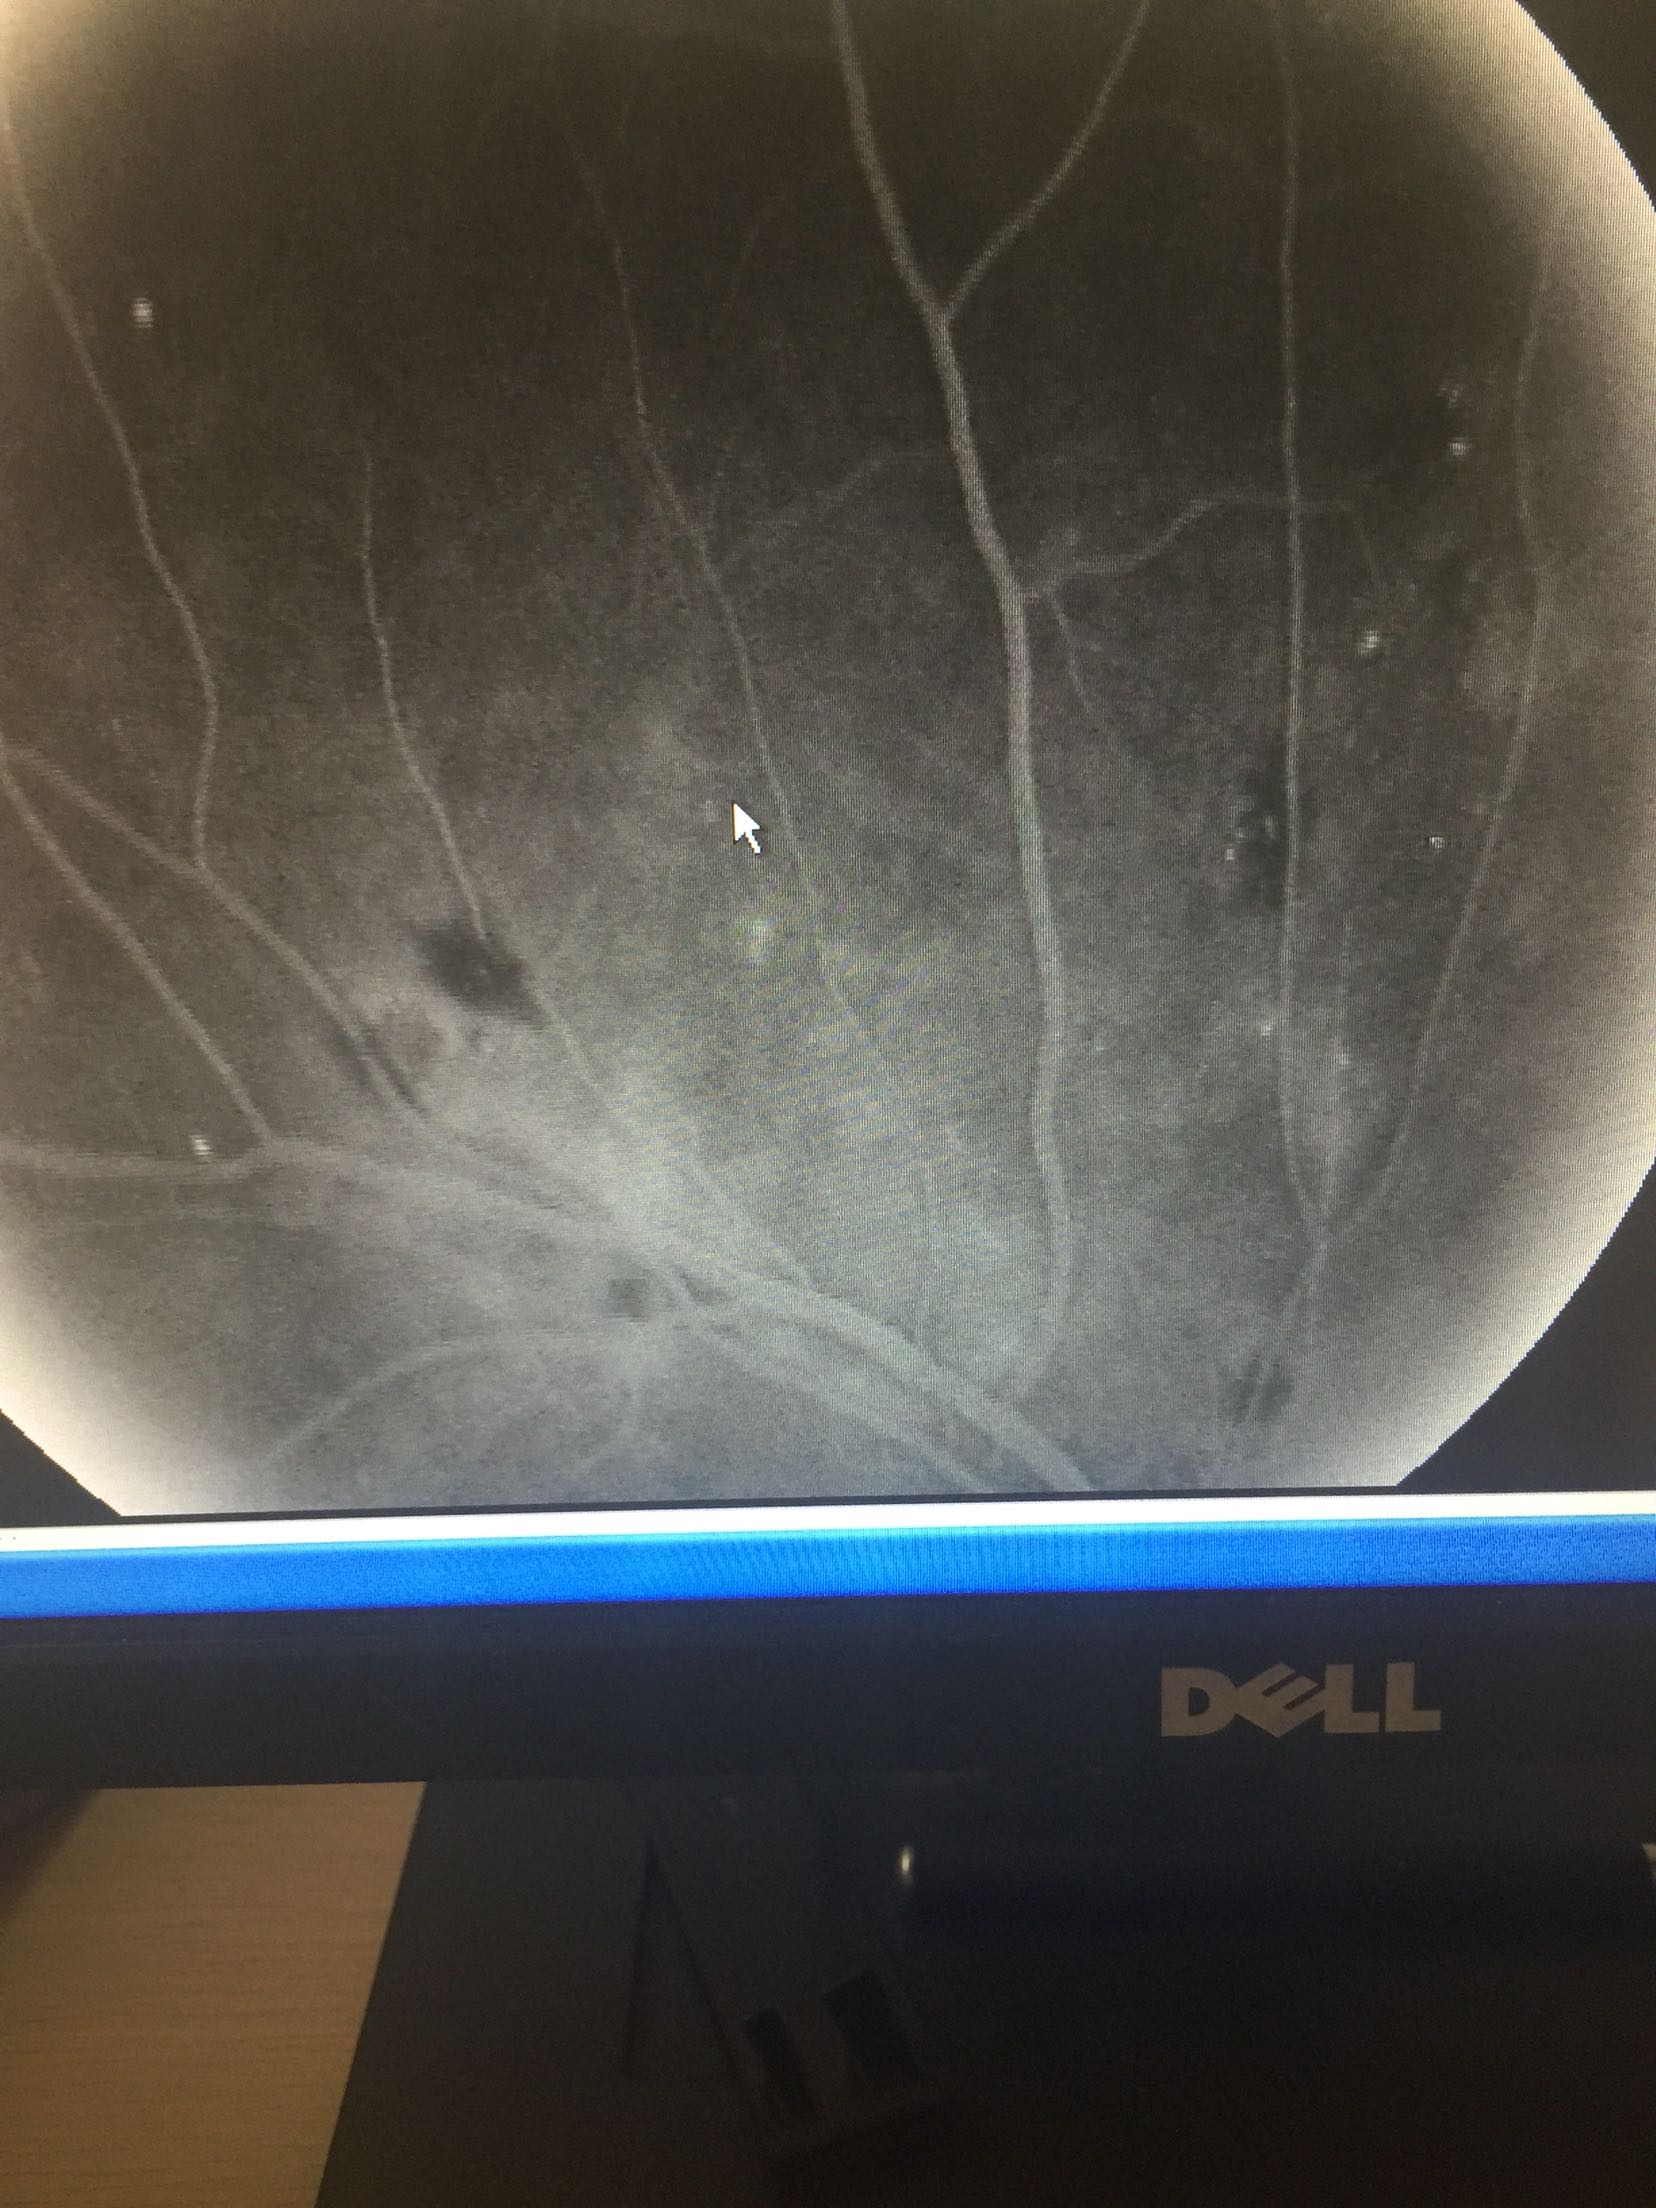

视力: 右眼0.6 左眼0.5 双眼睑无水肿,结膜无充血,角膜透明,前房正常,瞳孔圆,对光反射可,虹膜纹理清,晶体轻度浑浊,眼底视盘界清色可,黄斑区中心凹反光还可,网膜散在片状出血及硬性渗出 眼压:13/17 血压100/70mmhg 随机血糖:6.2

心电图:窦性心律,67次/分 造影:左眼动脉充盈时间为23秒,静脉充盈时间为27.2秒,双眼全视网膜可见片状荧光遮蔽及黄白色硬性渗出,早期双眼全视网膜散在点状高荧光,晚期有荧光渗漏

双眼糖尿病视网膜病变 药物促进血液吸收,改善眼底循环,视网膜光凝治疗